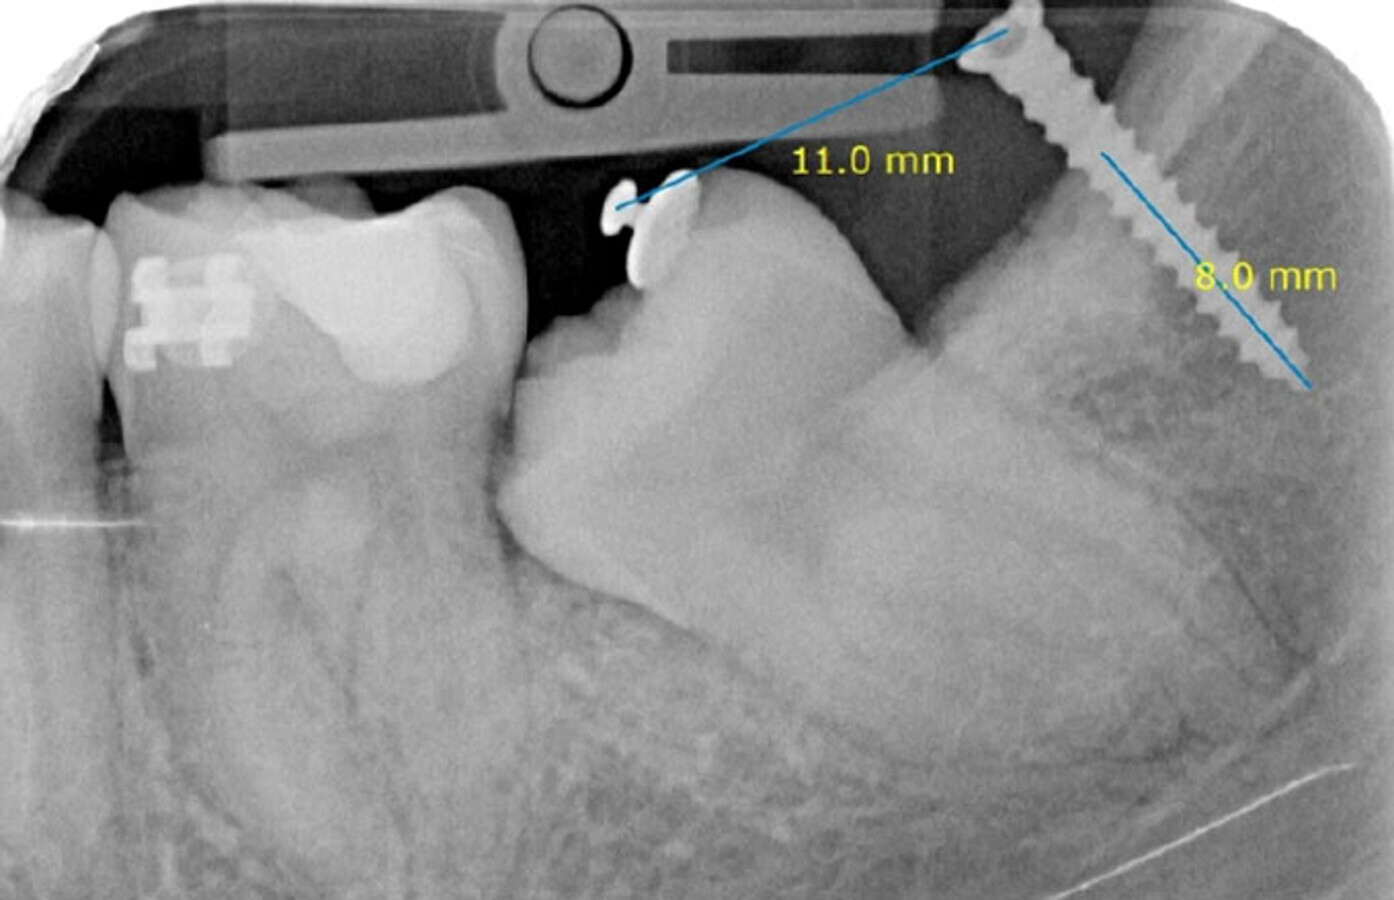

Rx de control tracción botón (inicio).

Rx de control tracción botón (final).

Aproximadamente 6 meses después, se prepara un anclaje esquelético con un tornillo de titanio autoperforante (D2.0 / L 12mm, Jeil Medical Corporation). Estos tornillos son más indicados para fijar injertos en bloque. Este anclaje permite enderezar el segundo molar por completo. En una primera fase, se tracciona desde el tornillo a un botón colocado en la cúspide distolingual del diente 37 con cadeneta elástica. Una vez el diente 37 está “desenclavado”, se termina de enderezar, cementando estratégicamente brackets y tubos de cementado directo y utilizando arcos elásticos NiTi.